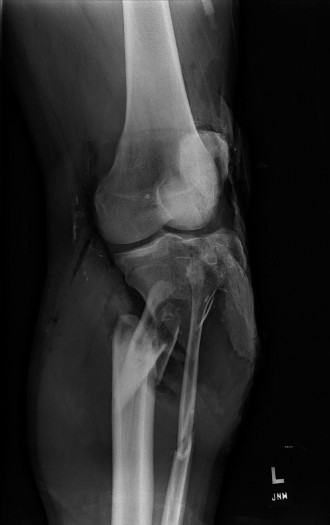

A 48-year-old woman presents to the emergency department complaining of acute left knee pain and inability to…

A 48-year-old female patient presents with anterior left knee pain. She has had a history of recurrent patell…